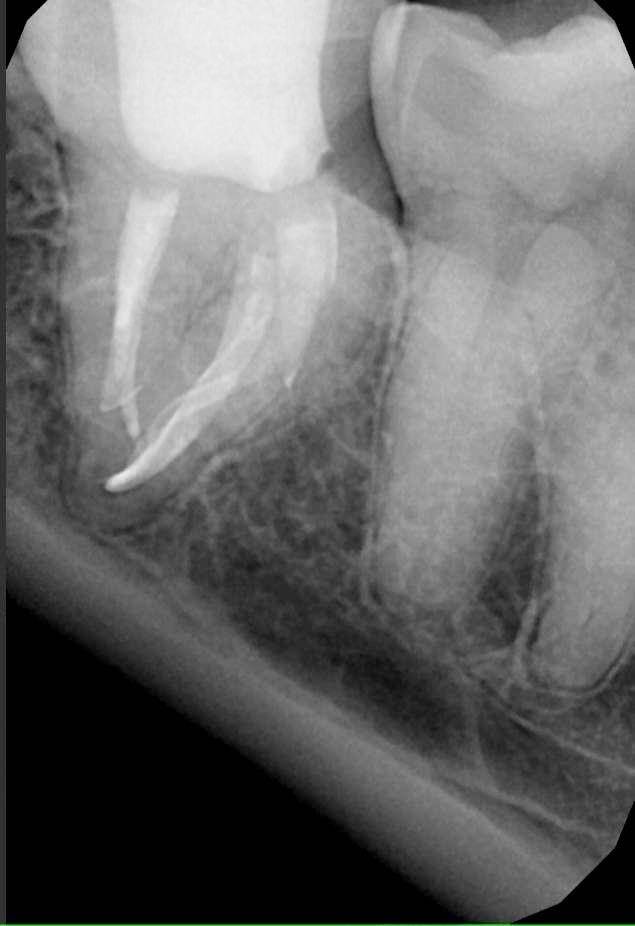

Гарриевич Опубликовано 31 января Автор Поделиться Опубликовано 31 января Когда в твоем кресле оказывается пациент с редким заболеванием «стоматолог-терапевт» работать всегда… легче. Именно! Потому что ты на 100% уверен, что этот человек понимает разницу между «гарантия» и «прогноз», а он на 100% уверен, что ты тот кто ему нужен. Зуб 4.7 со сложной анатомией, ступенькой в мезиальной системе, двойным изгибом, пропущенным каналом и апикальным периодонтитом. Реколл 1 год И сам осмотр через 1 год 4 1 1 Ссылка на комментарий

Гарриевич Опубликовано 13 марта Автор Поделиться Опубликовано 13 марта (изменено) Изменено 13 марта пользователем Гарриевич 2 1 1 Ссылка на комментарий